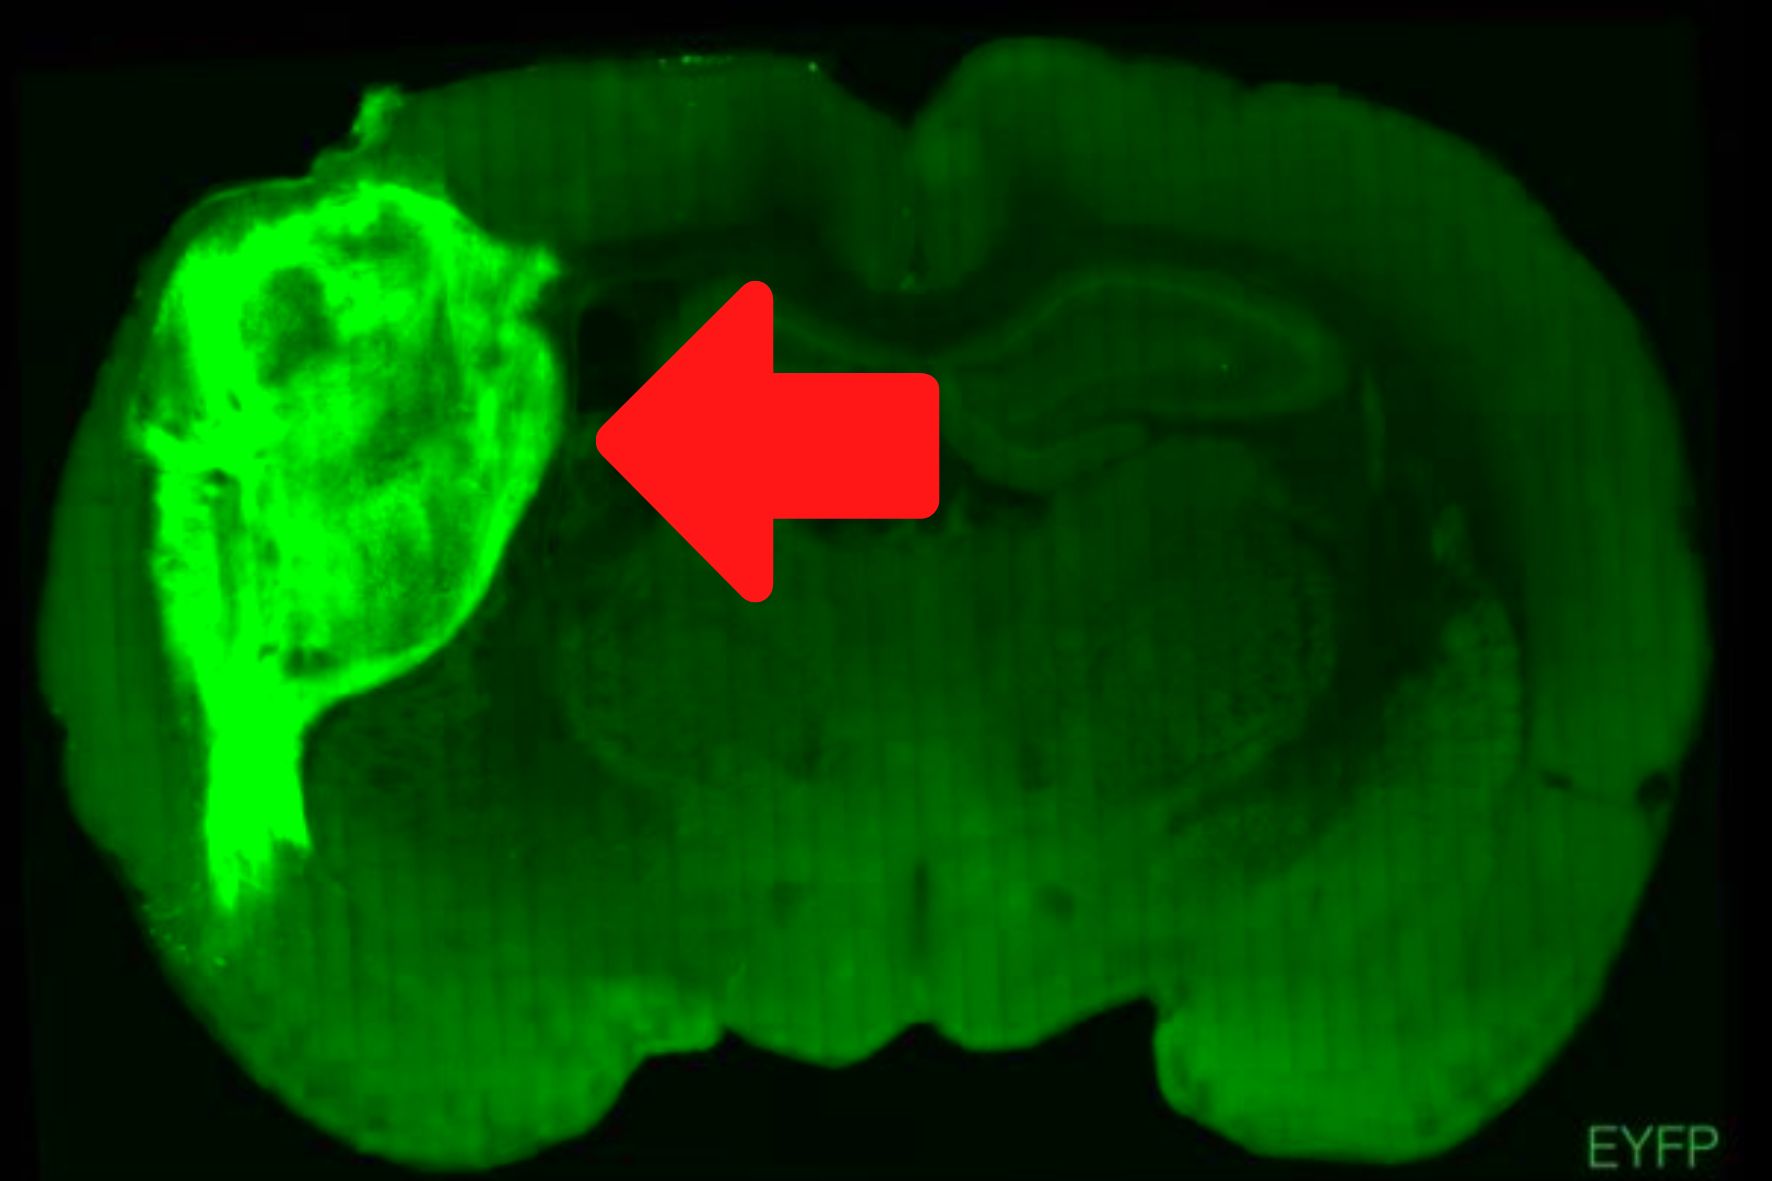

ヒト脳オルガノイドをラット脳に移植し接合することに成功! - ナゾロジー

ヒトの脳細胞を持つラットは、ラットなのでしょうか?米国のスタンフォード大学(Stanford University)で行われた研究によれば、人間の人工培養脳(ヒト脳オルガノイド)をラットの赤ちゃんに移植したところ、ラットの脳の一部として統合...

| B:合成生物学とな。倫理的に許されるかどうかは不明らしいが。腑に落ちないのは俺だけか? |